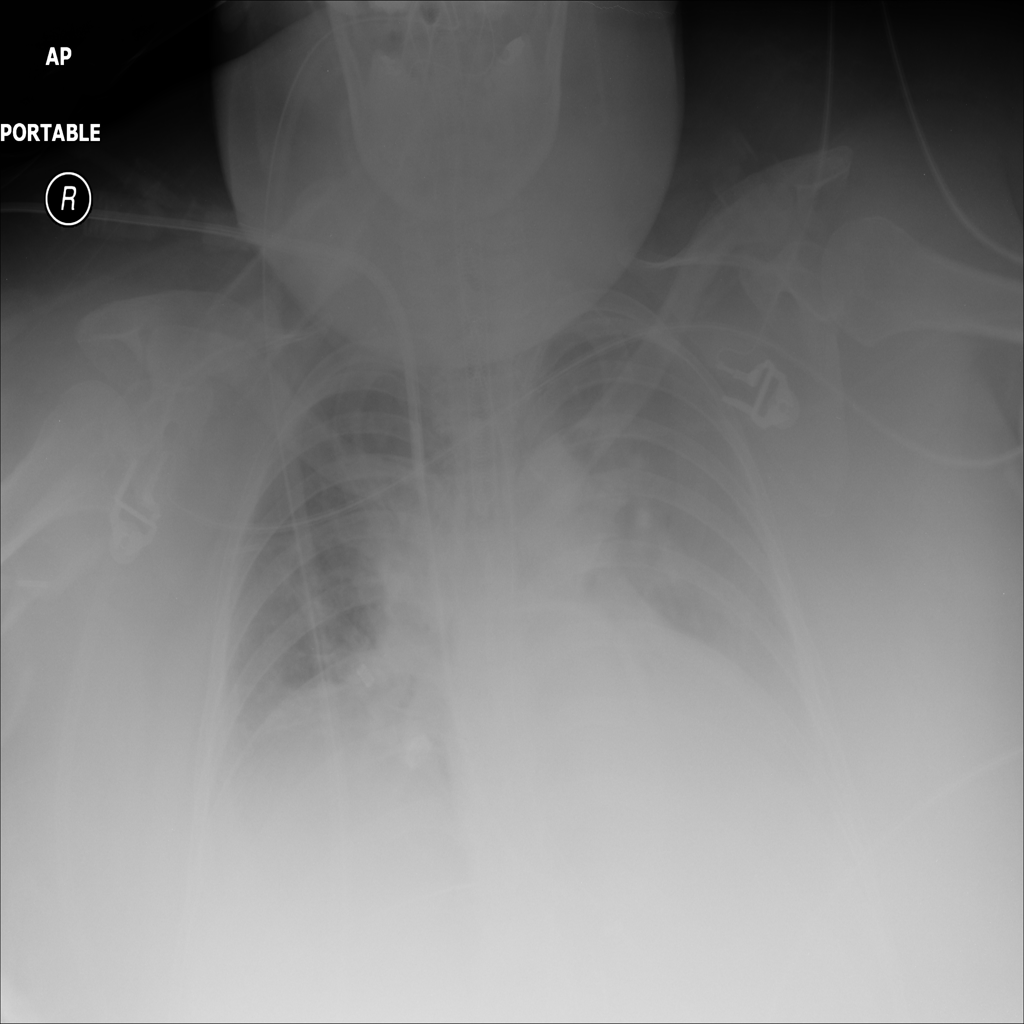

PAT-DB80 · IMG-000Atelectasis

PAT-DB80 · IMG-000

PA